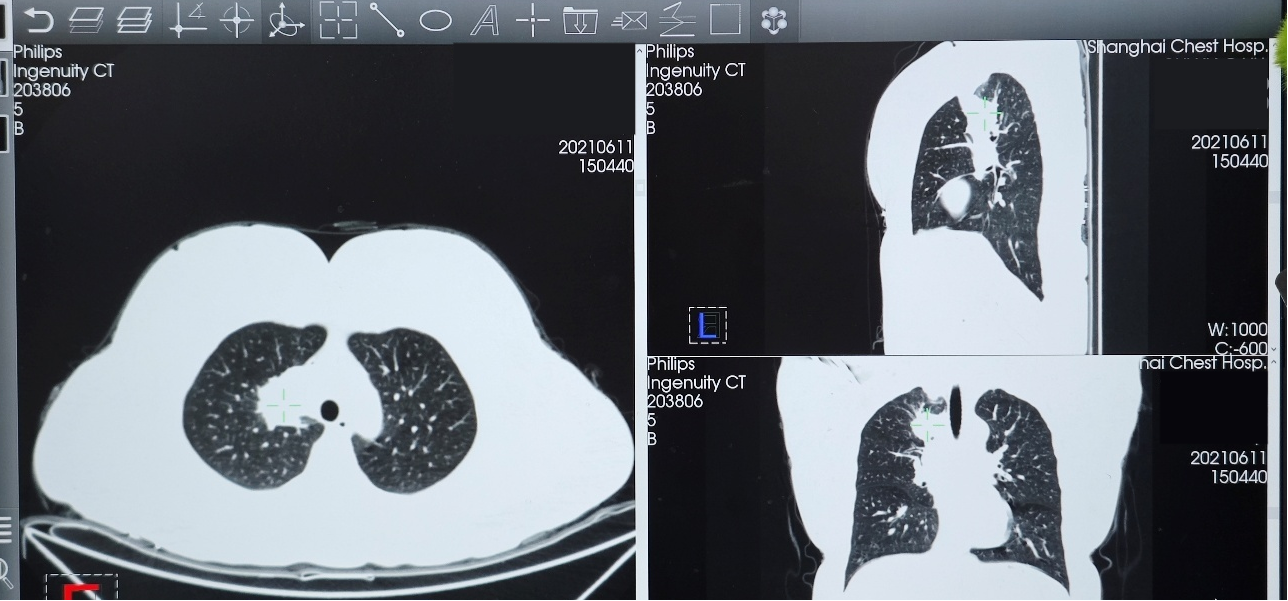

● 胸部CT(2021年6月11日):右肺上叶实性肿块影,大小约34×33mm,考虑肺癌;右肺门及纵隔淋巴结肿大。两肺多发微小结节。

2023年10月24日复查胸部CT,示右肺上叶实性肿块影,大小约37×15mm,与2023年8月25日CT相比病灶增大,评估为靶向治疗耐药导致疾病进展(PD)。

第一阶段:2024年1月19日首次复查,肺部病灶较前缩小,大小约34×11mm;2024年4月22日复查,肺部病灶较老片相仿,疗效评价维持SD,治疗方案调整为“培美曲塞+PD-1单抗+贝伐珠单抗”,并开始使用双膦酸盐进行骨保护治疗。